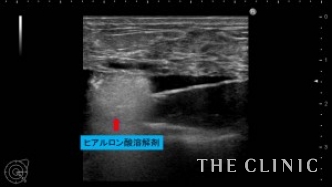

昨年12月にヒアルロン酸豊胸の手術を受けたが、2ヶ月前からしこりが気になり始めたため手術を受けたクリニックに相談に行くと、しこり除去後2~3ヶ月経たないと脂肪注入は出来ないと言われたそうです。患者様はそんなに待てないとのことでヒアルロン酸除去とCRF豊胸のご相談で当院にいらっしゃいました。エコーで確認すると、乳腺と大胸筋の間にヒアルロン酸がたくさん残っており、一部カプセルを形成してしこりになっていました。CRF豊胸を行う前にヒアルロン酸を溶解除去しないと、コンデンスリッチファットの定着が下がる可能性があるため、エコー下に確実に吸引除去する必要があります。ヒアルロン酸が少量であれば、ヒアルロン酸除去と同時にCRF豊胸が可能ですが、この方は大量にヒアルロン酸が残っていたため、まずはヒアルロン酸除去を行いました。

16ゲージの注射針を確実にヒアルロン酸のしこりに入れて、ヒアルロニダーゼ(ヒアルロン酸溶解剤)を注入し、溶けたヒアルロン酸は吸引除去します。

両側合わせて150㏄のヒアルロン酸を吸引除去しました。

ヒアルロン酸注入によるしこりのエコー診断カルテ